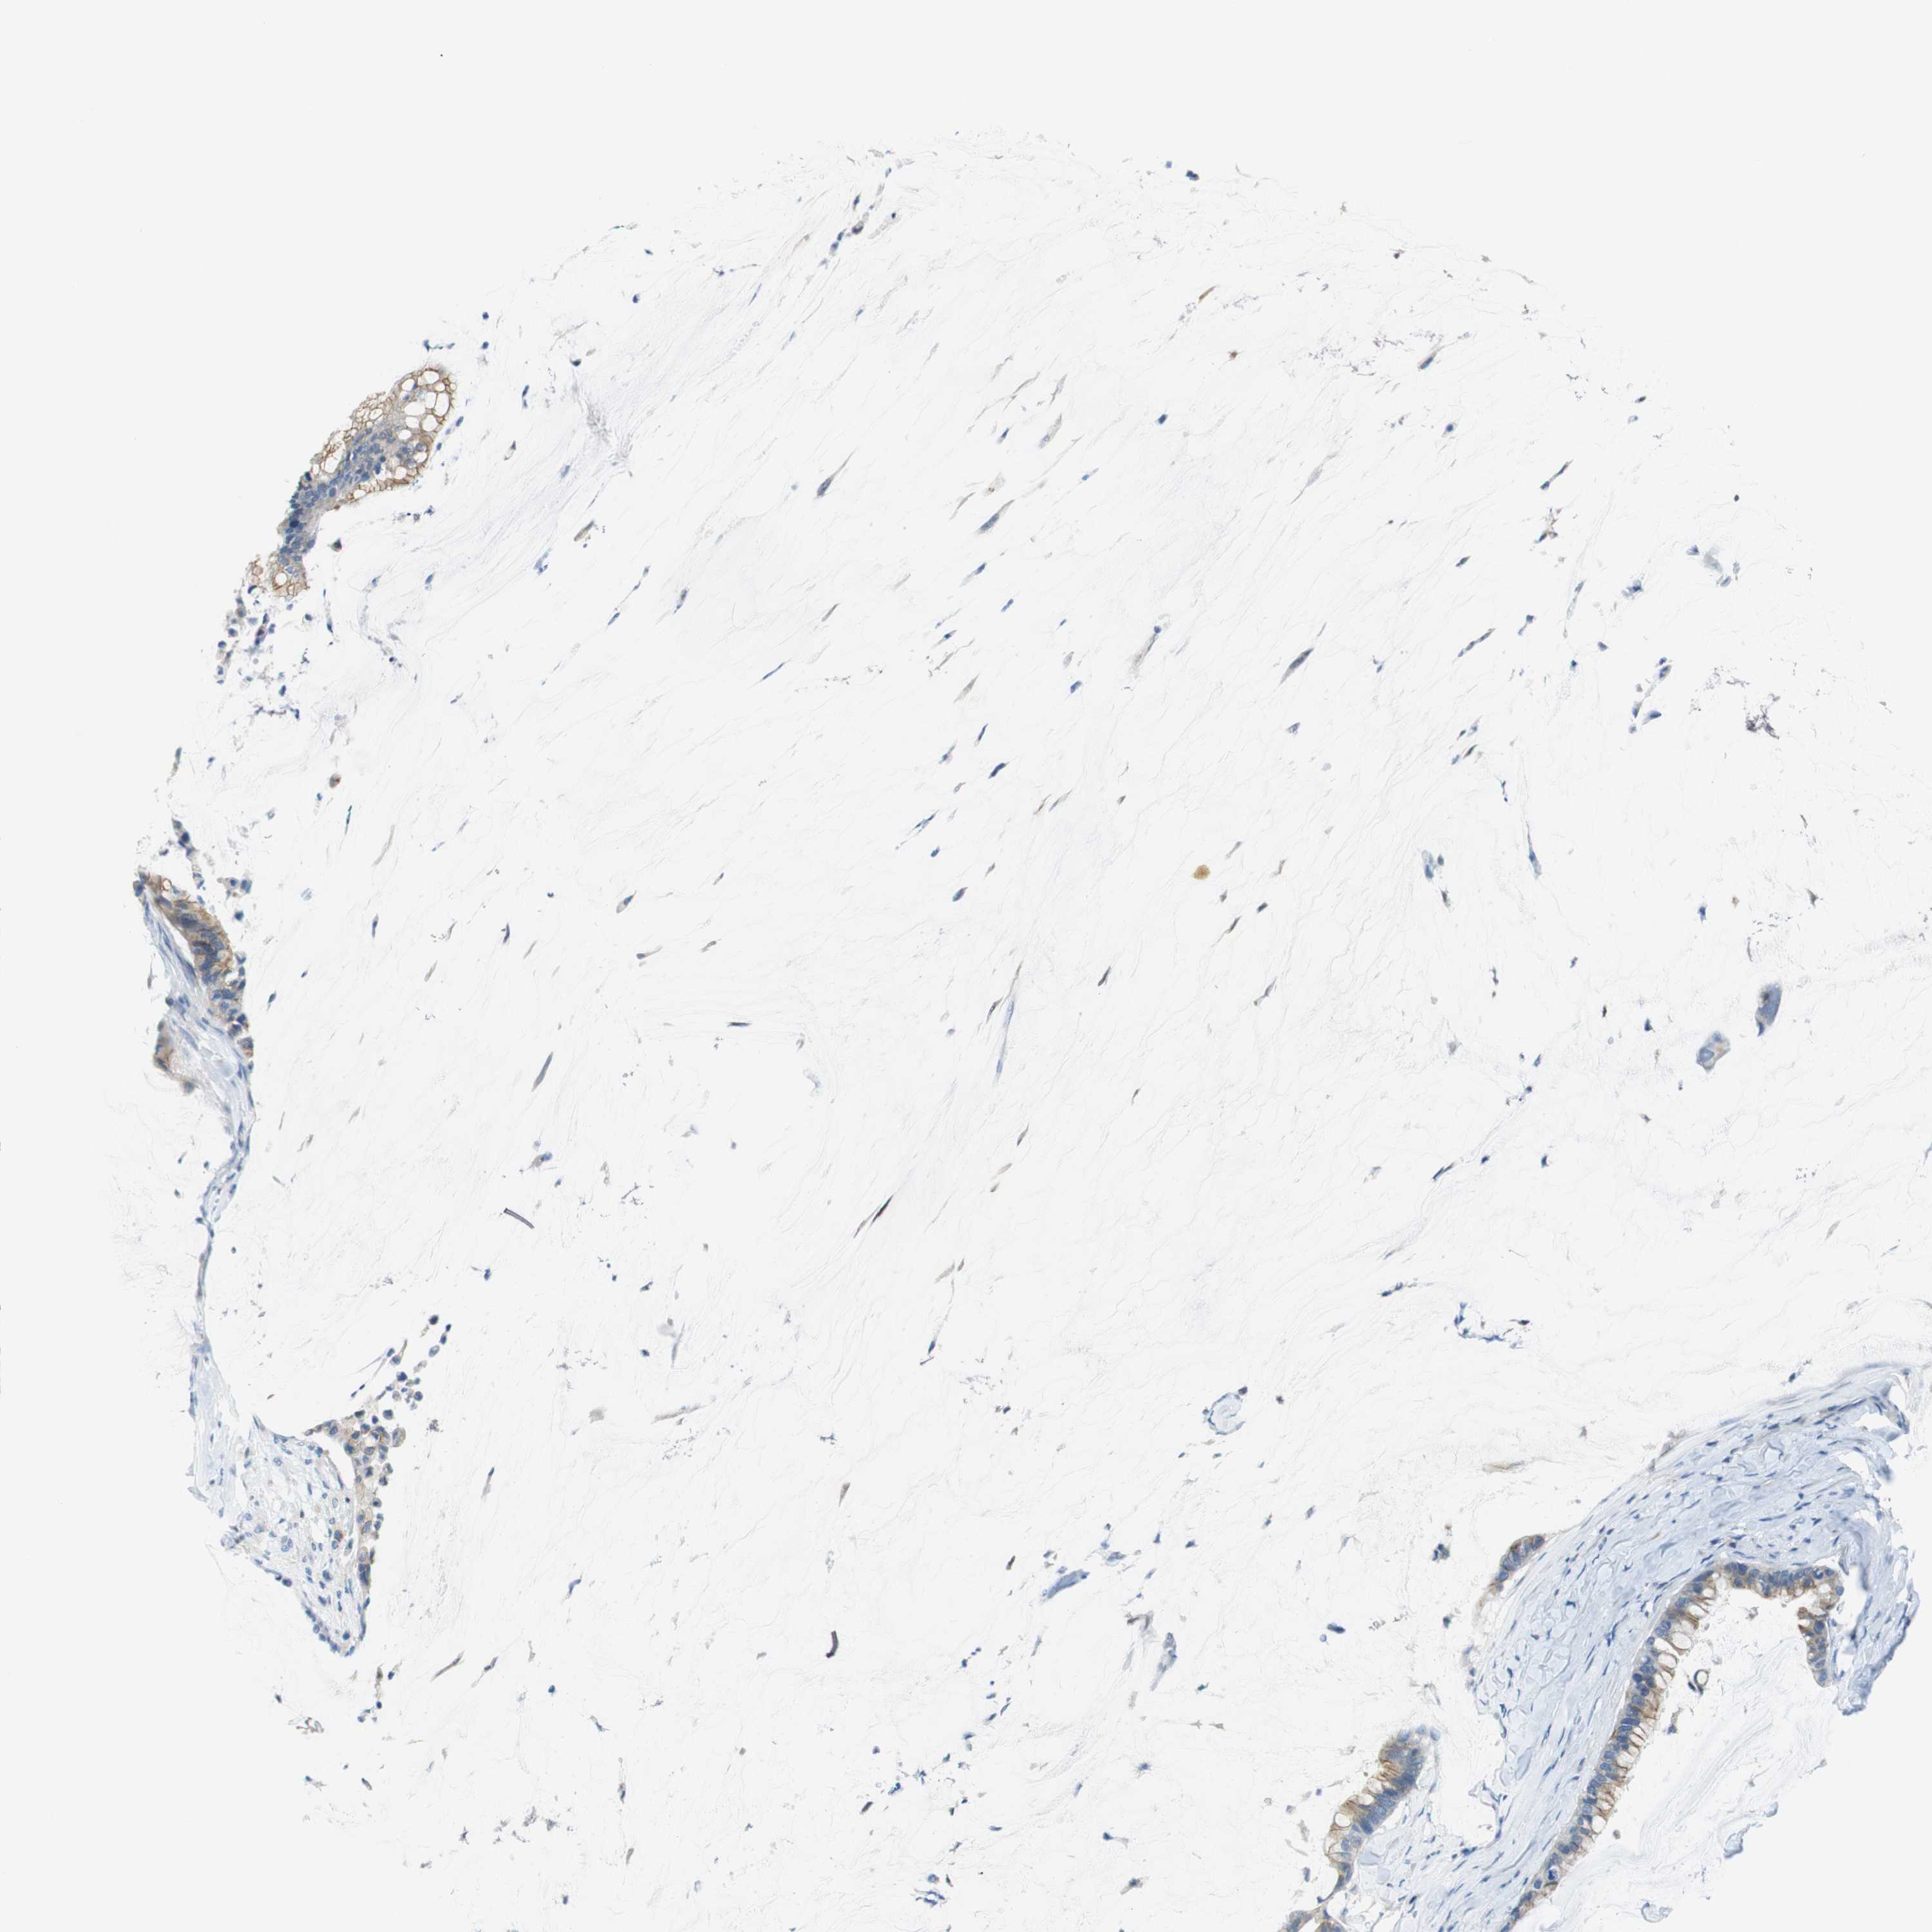

PANCREATIC CANCER - Protein expressioni

A mouse-over function shows sample information and annotation data. Click on an image to view it in a full screen mode. Samples can be filtered based on level of antibody staining by selecting one or several of the following categories: high, medium, low and not detected. The assay and annotation is described here.

Note that samples used for immunohistochemistry by the Human Protein Atlas do not correspond to samples in the TCGA dataset.

Antibody stainingi

Antibody staining in the annotated cell types in the current human tissue is reported as not detected, low, medium, or high, based on conventional immunohistochemistry profiling in selected tissues. This score is based on the combination of the staining intensity and fraction of stained cells.

Each image is clickable and will lead to virtual microscopy that enables deeper exploration of all samples and also displays staining intensity scores, fraction scores and subcellular localization as well as patient and tissue information for each sample.

Antibody HPA012634

Staining

High

Medium

Low

Not detected

Intensity

Strong

Moderate

Weak

Negative

Quantity

>75%

75%-25%

<25%

None

Location

Nuclear

Cytoplasmic/membranous

Cytoplasmic/membranous,nuclear

Adenocarcinoma, NOS